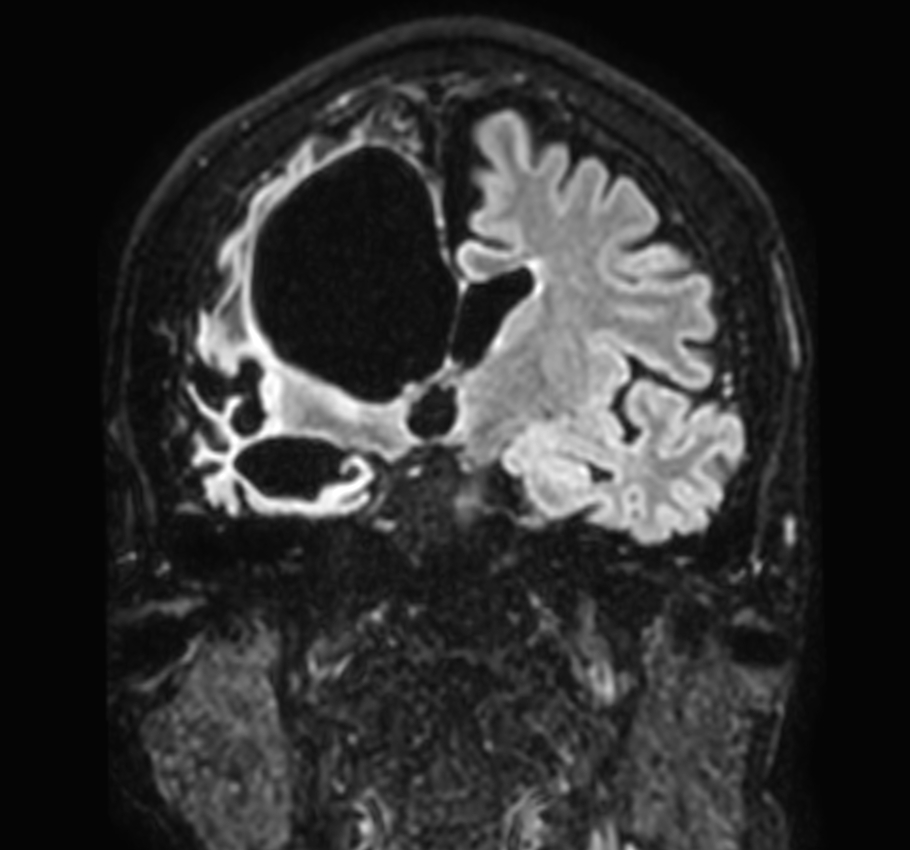

Coronal 3D BrainVIEW FLAIR (without Compressed SENSE)

Coronal 3D BrainVIEW FLAIR (Compressed SENSE)